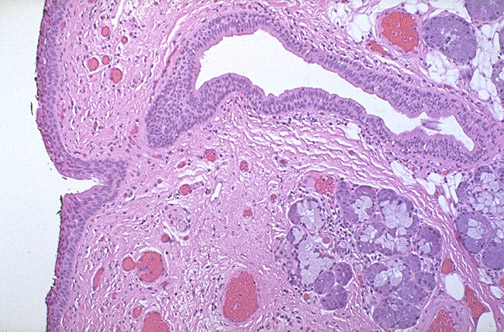

This is the nasopharynx, with a

pseudostratified epithelium

overlying a submucosa that contains prominent

mucus-secreting glands

.